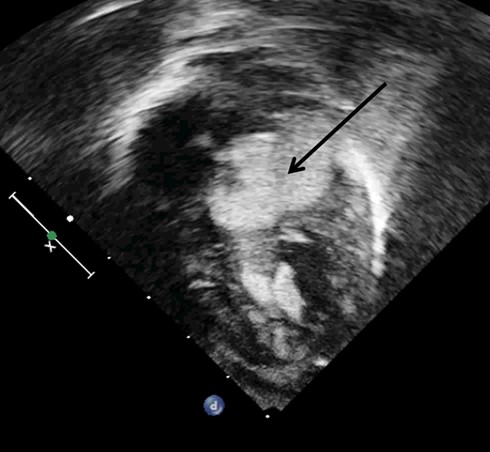

Новорожденный кардиоребенок был доставлен в Красноярский кардиоцентр из Хакасии на 8 сутки жизни. Его вес был меньше 3-х кг, при этом у него были выявлены множественные новообразования сердца. Основная проблема заключалась в том, что самое большое образование перекрывало выход в аорту, что создавало угрозу жизни. Обследовав все органы и системы, других патологий у ребенка не выявлено, это означало, что у ребенка есть шанс на здоровую жизнь в будущем.

Опухоли сердца у детей - редкая патология, которая встречается в 1 случае на 10 000 или 0,08% среди всех патологий сердца. Наиболее частыми из них являются рабдомиомы, которые возникают еще внутриутробно. Это доброкачественная опухоль, которая уменьшается по мере роста ребенка, оперировать ее нужно только в случае нарушения кровотока, связанного с локализацией опухоли.

«Я впервые видел сердце, буквально нашпигованное опухолями. Нам предстояло убрать опухоль в аорте, диаметр которой 8 мм, при этом, не травмировать аортальный клапан. Риск операции был очень большой, но это давало ребенку шанс на жизнь и на выздоровление. Мы рискнули и получили хороший результат. На операции оказалось, что опухоль, к тому же, была сращена с одной из створок аортального клапана и ее пришлось буквально отрезать от нее», - рассказывает заведующий детским кардиохирургическим отделением Федерального центра сердечно-сосудистой хирургии Красноярска Павел Теплов.